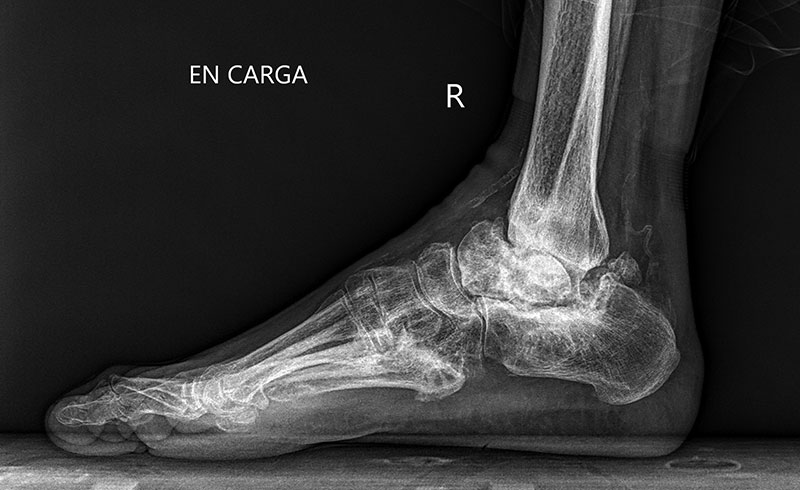

Antes